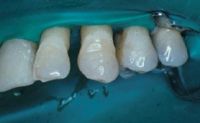

Se aislaron los dientes durante el procedimiento clínico con un dique de goma que se extendió a los primeros premolares. Debido a que los dientes tienen movilidad el dique es de fácil de colocar. Es especialmente importante que los agujeros perforados para el dique de goma dejen al menos 2 mm de dique entre espacios y que los agujeros para los incisivos mandibulares sean tan pequeños como sea posible.

Los dientes se limpiaron en la superficie facial y lingual utilizando una copa de profilaxis con una pasta de piedra pómez no fluorada. Los dientes fueron aclarados y secados completamente. Las superficies interproximales de los dientes se limpiaron y se prepararon con CeriSander (Den-Mat, Santa María, CA) una tira de diamante para acabado de grano medio sujeta en una segueta.

Para minimizar el volumen de la férula se realiza una preparación definitiva de los dientes en las superficies linguales del #22-27, utilizando una fresa de 330 con una profundidad de entre 0,5 y 1 mm. La anchura del canal se determina por el ancho de la fibra Ribbond seleccionada. En la mayoría de los casos no será necesario anestesia porque la preparación sólo se hará en el esmalte. El canal de preparación se extiende sólo a la mitad mesial de los caninos.

Otra ventaja de usar una preparación de canal es que la cinta de refuerzo Ribbond recortada se coloca fácilmente en este durante el procedimiento de restauración.

Con este paciente los dientes se prepararon utilizando una fresa de 330 con un canal de 1 mm de profundidad y anchura de 3 mm para dar cabida a una fibra Ribbond de 3 mm de ancho. La preparación adicional del diente en la cara interproximal también se hizo utilizando una fresa de diamante puntiaguda de composición fina para dejar espacio adicional para el composite.